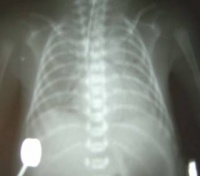

1、胸部X线检查

两肺有无肺纹理增加、斑片状阴影或两肺广泛密度增加及呈“白肺”外观;恢复期病变吸收可表现为网状和线状阴影,有时用X线可不留异常表现。

2.胸部X线表现:早期可无异常或有纹理增多,边缘模糊。病情进展后出现斑片状阴影,逐渐扩展形成大片实变。